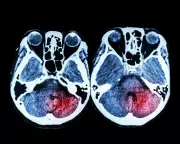

Exclusive: Seven stroke centres in England still lack 24/7 mechanical thrombectomy, risking patient lives and disabilities despite government promises and funding.